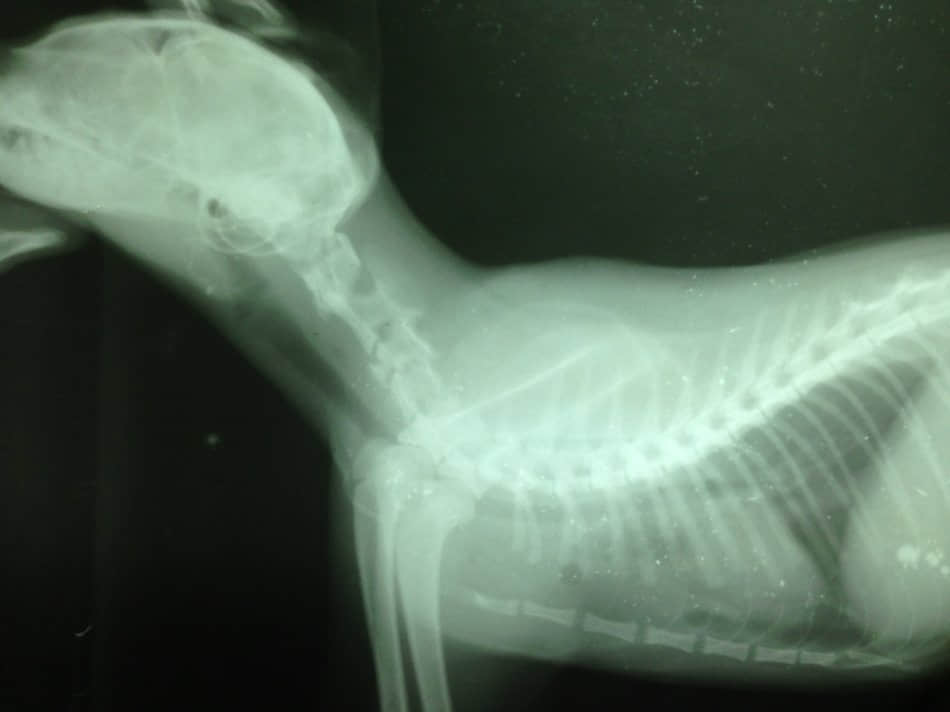

X-RAY显示第三颈椎压缩性骨折(如下图)。